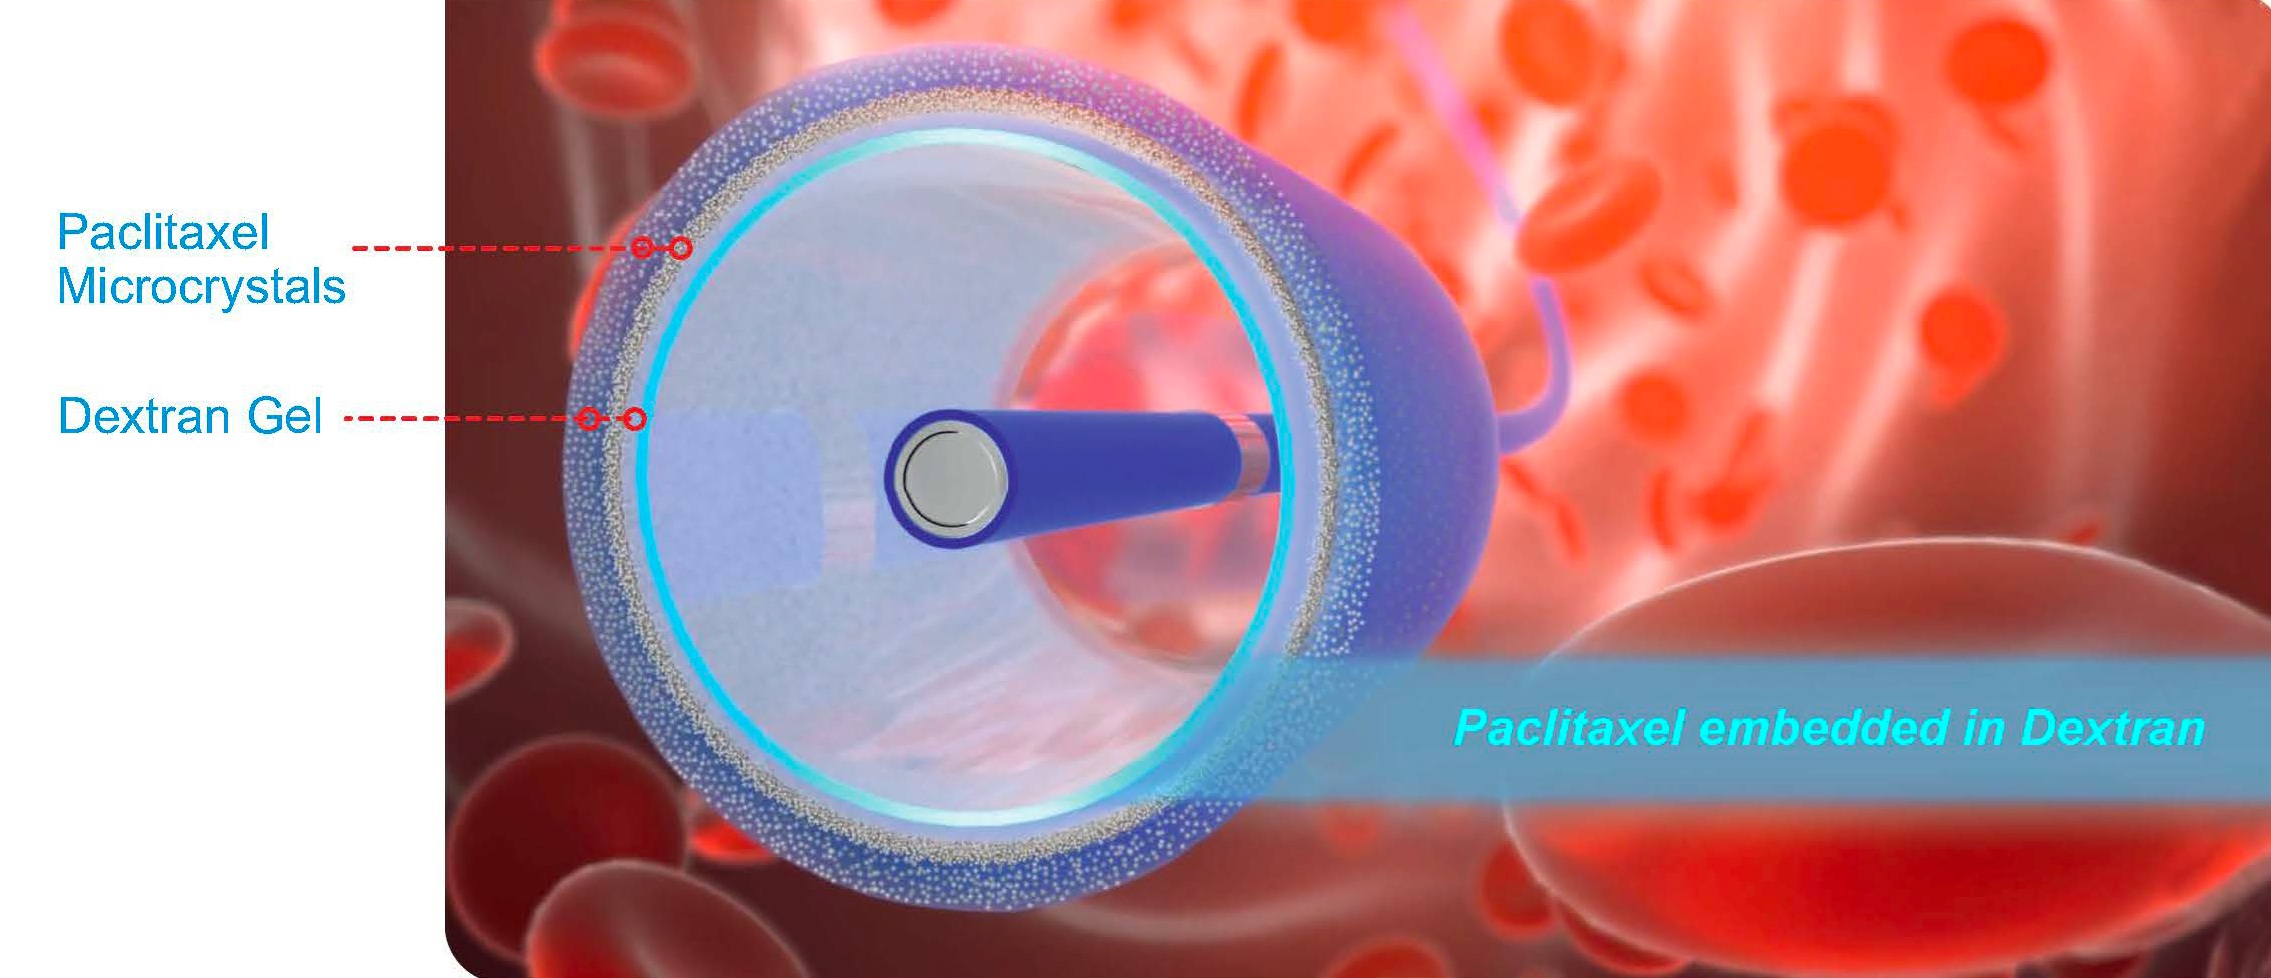

Τα N-ELUTAX “3” αποτελούν τρίτης γενιάς μπαλόνια με επικάλυψη διπλού φαρμάκου (Paclitaxel και Dextran), σχεδιασμένα για την αντιμετώπιση στενώσεων σε ενδοκρανιακές και καρωτιδικές αρτηρίες μέσω μηχανικής διάτασης και στοχευμένης φαρμακευτικής δράσης. Η μοναδική τεχνολογία τρισδιάστατης μήτρας (3D Dextran–Paclitaxel Matrix) εξασφαλίζει:

- Συνδυασμένη αντιμιτωτική και αντιθρομβωτική δράση

- Ελάχιστη απώλεια φαρμάκου (<5%) κατά τη διέλευση και το φούσκωμα του μπαλονιού.

- Αξιόπιστη και παρατεταμένη απελευθέρωση του φαρμάκου στο τοίχωμα του αγγείου με μια μόνο έκπτυξη, με θεραπευτική δράση που διαρκεί εβδομάδες.